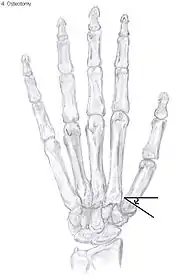

Osteotomy of the thumb

Metacarpal osteotomy

The aim of metacarpal osteotomy is to change the pressure distribution on the TMC joint. The hope is that this will slow the pace of development of osteoarthritis. There is no evidence that this procedure can modify the natural course of TMC OA. Osteotomy may be considered for people with mild arthritis.[24]

During osteotomy, the metacarpal is cut and a wedge shape bone fragment is removed to move the bone away from the hand.[36] Postoperative, the thumb of the patient is immobilized using a thumb-cast.

Possible complications are non-union of the bone, persistent pain related to unrecognized CMC or pantrapezial disease and radial sensory nerve injury.[24]